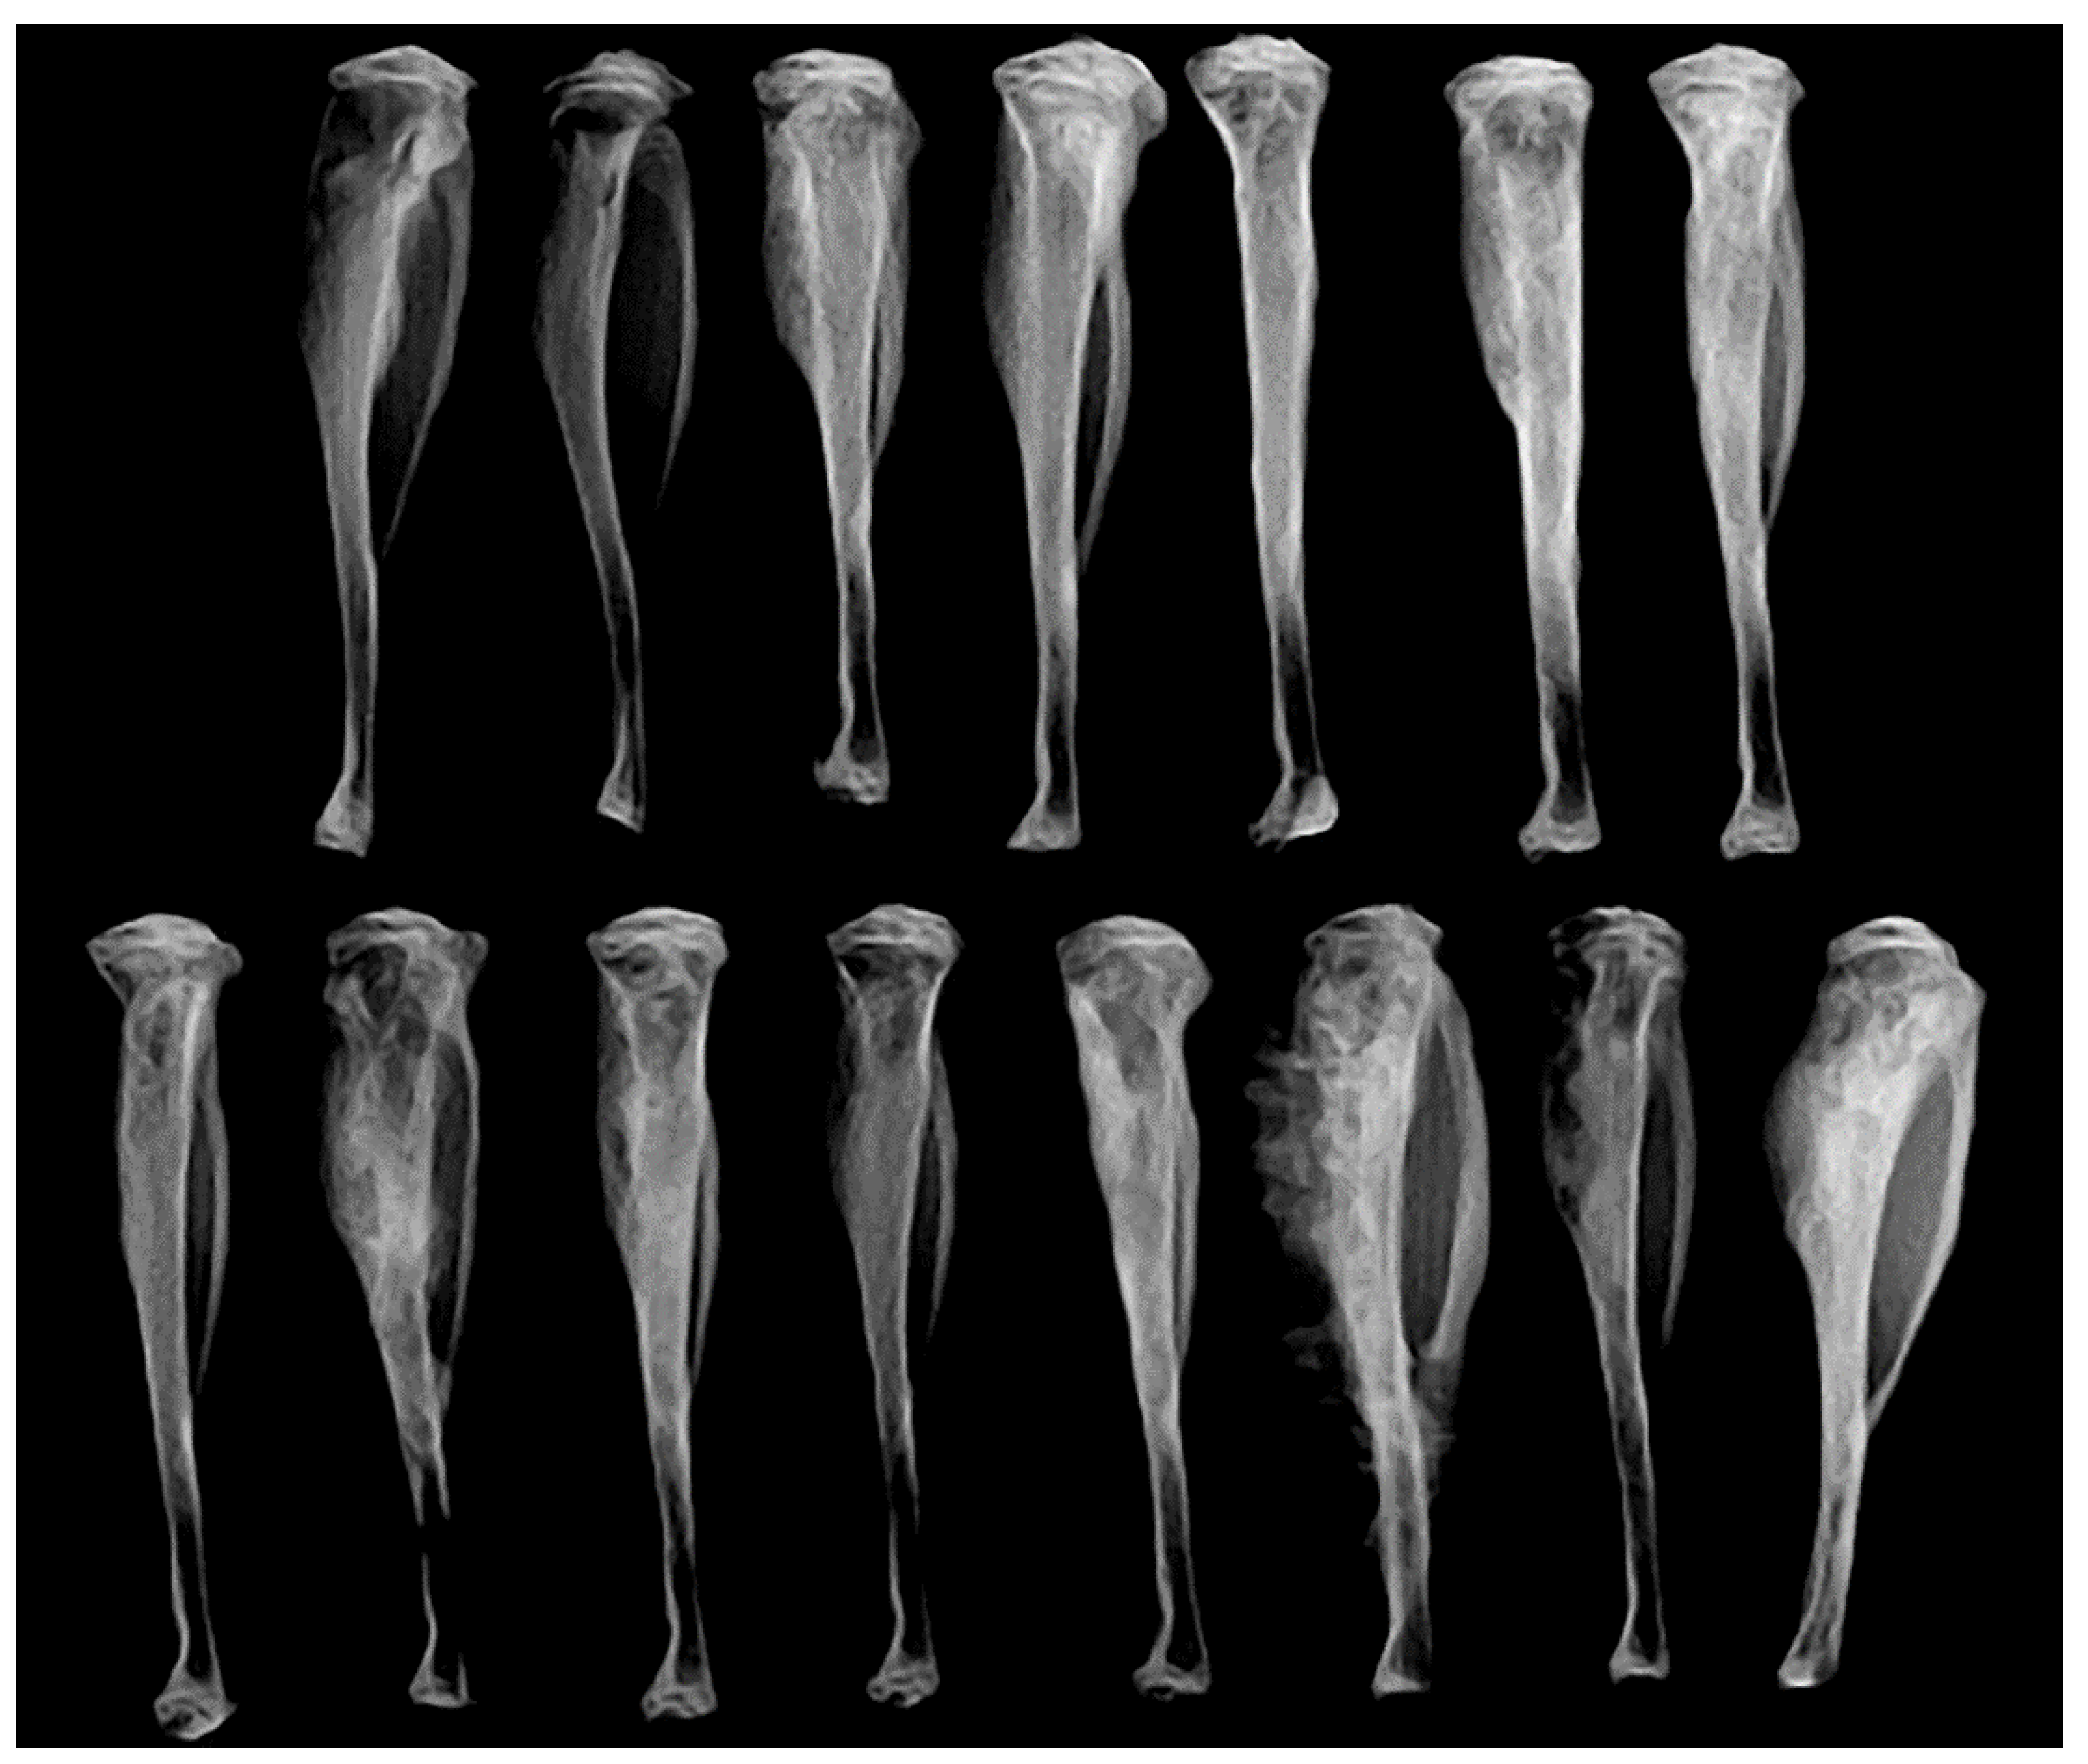

3.8. Intratibial Injection and JNK Inhibitor (SP600125) Treatment